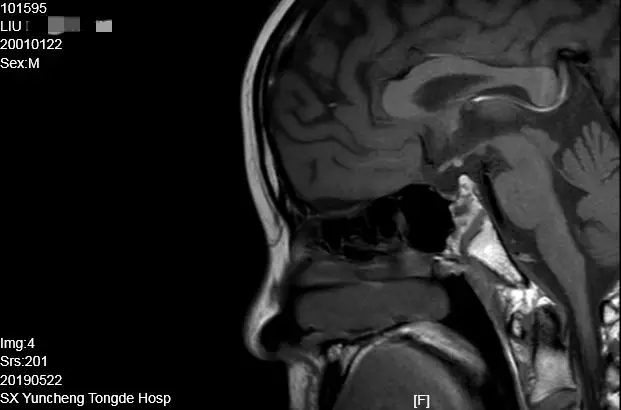

患者刘某,住院号101595

简要资料:男,18岁,大学在读,以“反复乏力、纳差、生长发育缓慢、间歇性意识障碍15年”入院。身高148cm,智力正常,嗅觉正常,无多尿。小阴茎,双侧隐睾,无阴毛。垂体MRI:腺垂体发育不良、垂体柄缺如、神经垂体异位到漏斗底部(化验室结果略)。

病例特点:青年男性,嗅觉正常,无多尿。身材矮小,无第二性征发育,原发性闭经,骨质疏松。肾上腺皮质轴、甲状腺轴、性腺轴和生长激素轴功能均减退。神经垂体异位,垂体柄消失。

最后诊断:1.异位神经垂体垂体柄阻断综合征;2.腺垂体功能减退症;3. 低促性腺激素性性腺功能减退症(HH);4.垂体性矮小症。

治疗方案:1.肾上腺轴:氢化可的松替代;2.甲状腺轴:优甲乐替代;3.性腺轴:绒促素、尿促素序贯治疗。因经济原因未进行重组人生长激素替代治疗。